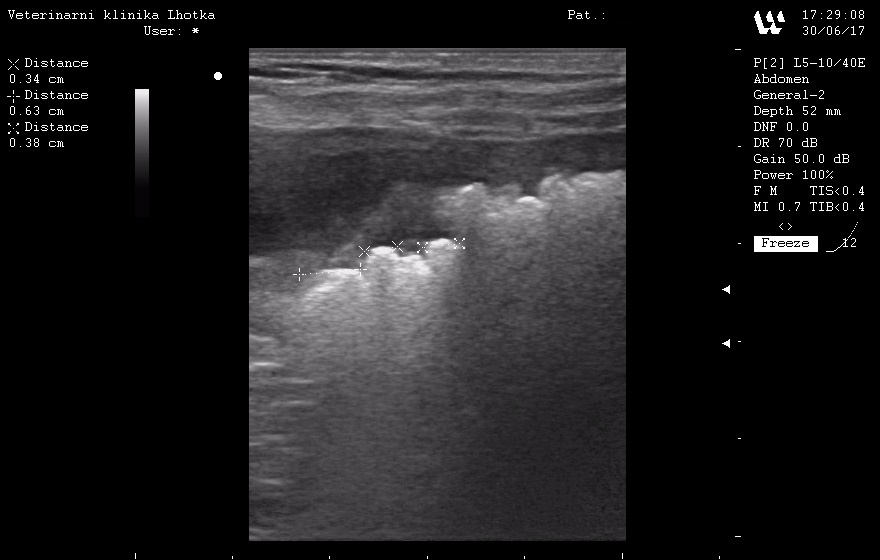

Při sonografickém vyšetření byl sice močový měchýř jen málo naplněný močí, zato byl plný drobných urolitů  od 2 do 7 mm.

SONO MM před operací 2.jpgSONO MM před operací 1.jpg